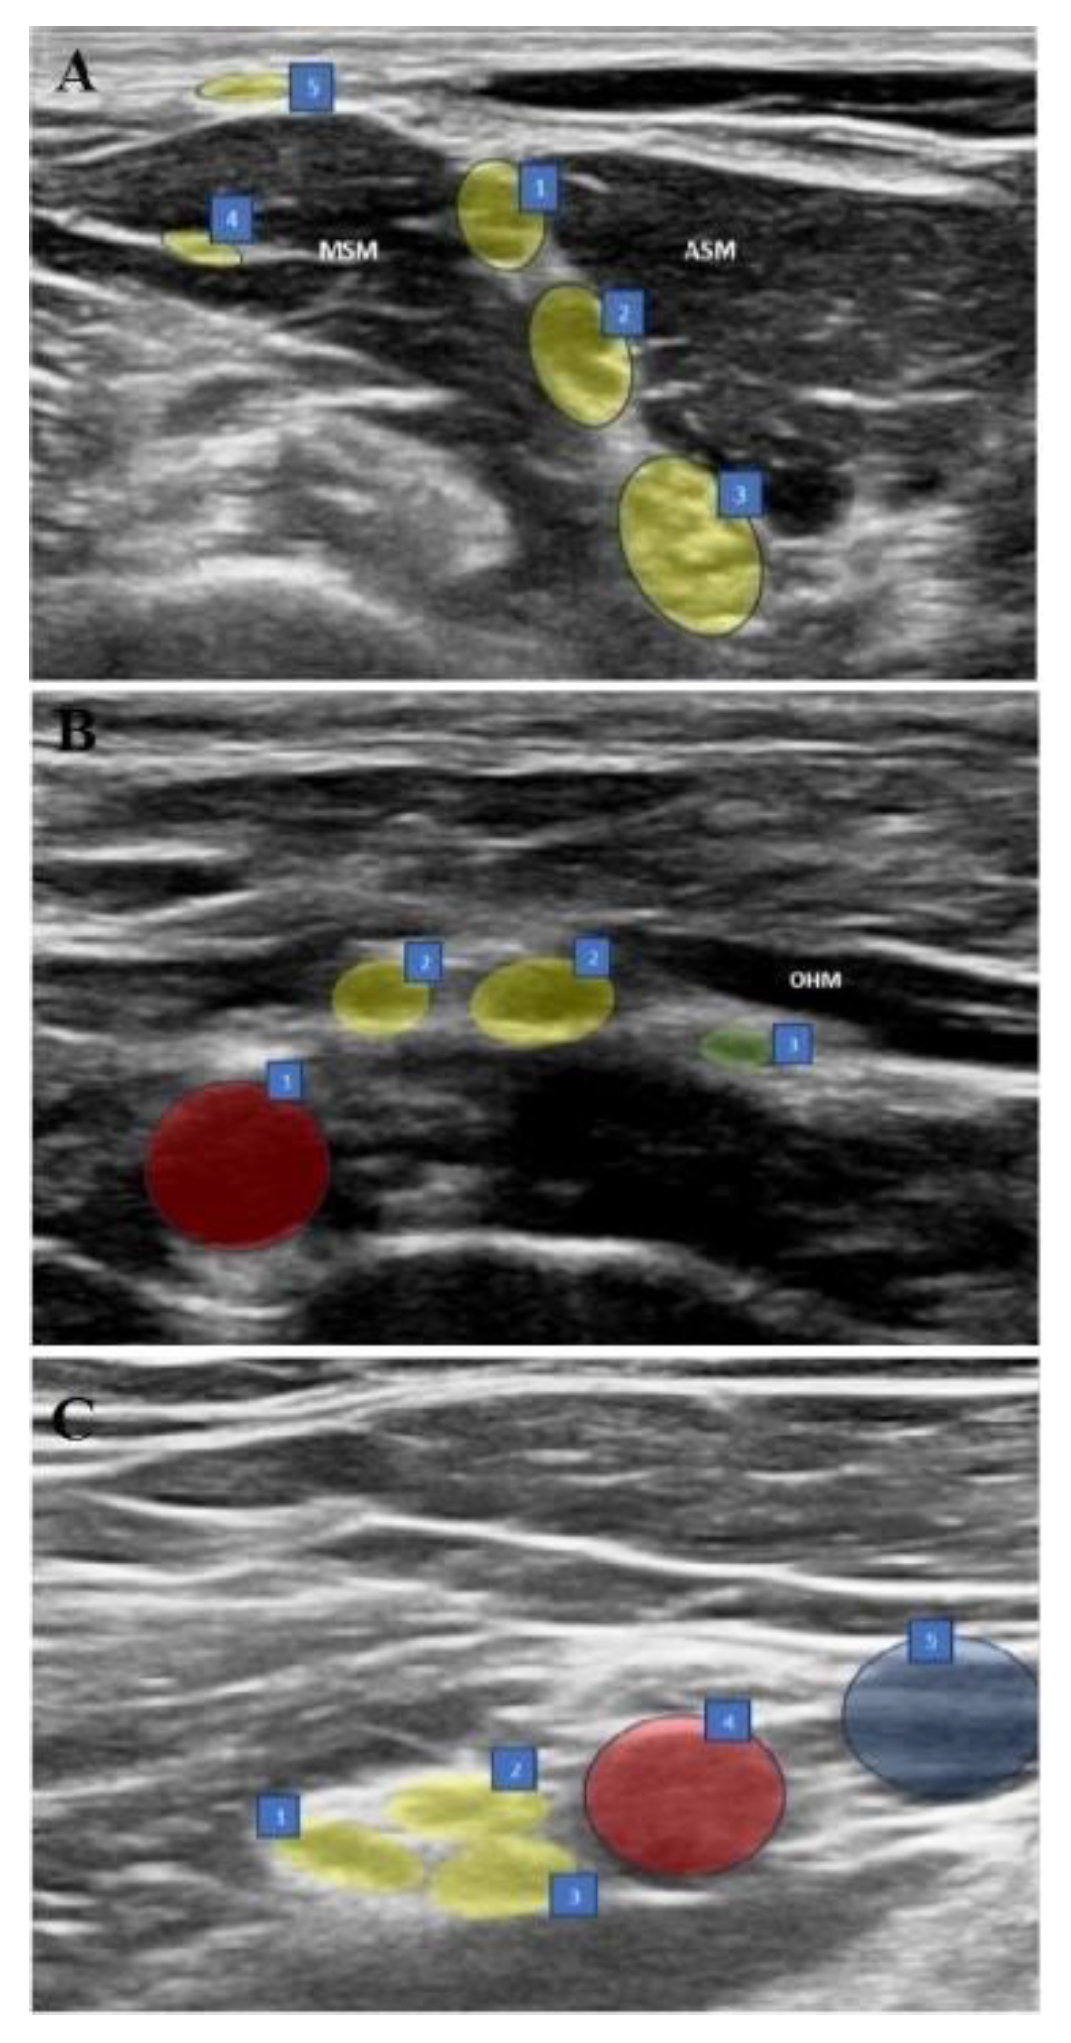

2.4. Interscalene Brachial Plexus Block (ISB) (Figure 1A)

In the supine position, with the arm adducted, the probe was placed transversely in the supraclavicular fossa just proximal to the midpoint of the clavicle. The brachial plexus was identified as a bright echogenic structure posterolateral to the subclavian artery (bunch of grapes sign). Then, the nerves were held in the center of the screen and the probe was moved in a cephalic direction up to the interscalene groove until a “string of pearls” image was obtained of the nerve roots located between the anterior and middle scalene muscles. After optimizing the image of the nerve roots as hypoechoic round or oval structures, the needle was placed posterolateral to the probe and moved in the plane. The needle was then located between the middle scalene muscle and the brachial plexus roots, and 15 ml of 0.25% bupivacaine was slowly injected into the area between the C5-6 roots.

Figure 1. Sonographic views of three blocks. (A) ISB: 1. C5 nerve root, 2. C6 nerve root, 3. C7 nerve root, 4. Long thoracic nerve, 5. Supraclavicular nerves, ASM: Anterior scalene muscle, MSM: Middle scalene muscle. (B) ASB: 1. Subclavian artery, 2. Upper trunk, 3. Suprascapular nerve, OHM: omohyoid muscle. (C) CCB: 1. Posterior cord, 2. Lateral cord, 3. Medial cord, 4.Axillary artery, 5.Axillary vein.

2.5. Anterior Suprascapular Nerve Block (ASB) (Figure 1B)

In the supine position, with the arm adducted, the probe was placed in the supraclavicular fossa to identify the brachial plexus. The plexus was then followed until the suprascapular nerve branching from the upper trunk was seen. The needle was advanced from posterolateral to anteromedial, and the most lateral transverse image of the nerve was obtained with the in-plane technique. The nerve was entered between the superficial cervical fascia and prevertebral fascia under the omohyoid muscle from the lateral side and 5 ml of 0.5% bupivacaine was injected following hydrodissection with DW5 and negative aspiration.

2.6. Costoclavicular Brachial Plexus Block (CCB) (Figure 1C)

The ipsilateral arm was abducted at 90 degrees with the palm facing the ceiling, and the ultrasound transducer was positioned parallel to the mid-clavicle. The long axis of the transducer was tilted slightly cephalad and the ultrasound beam was directed into the costoclavicular space. The ultrasound image was optimized so that all three cords of the brachial plexus were seen together lateral to the axillary artery, anteriorly between the clavicular head of the pectoralis major and the subclavius muscle and posteriorly between the serratus anterior muscle overlying the second rib. The needle was then advanced laterally and medially in the plane. With the needle tip in its intended position, a small volume (0.5-1 mL) of DW5 was injected before each injection to ensure that the needle tip was within the hyperechoic connective tissue matrix underlying the brachial plexus sheath and between the cords of the brachial plexus and not intraneurally. After verification, the local anesthetic was injected into multiple sites in 4-5 mL aliquots by redirecting the needle, for a total of 20 mL of 0.25% bupivacaine to homogeneously distribute the local anesthetic.